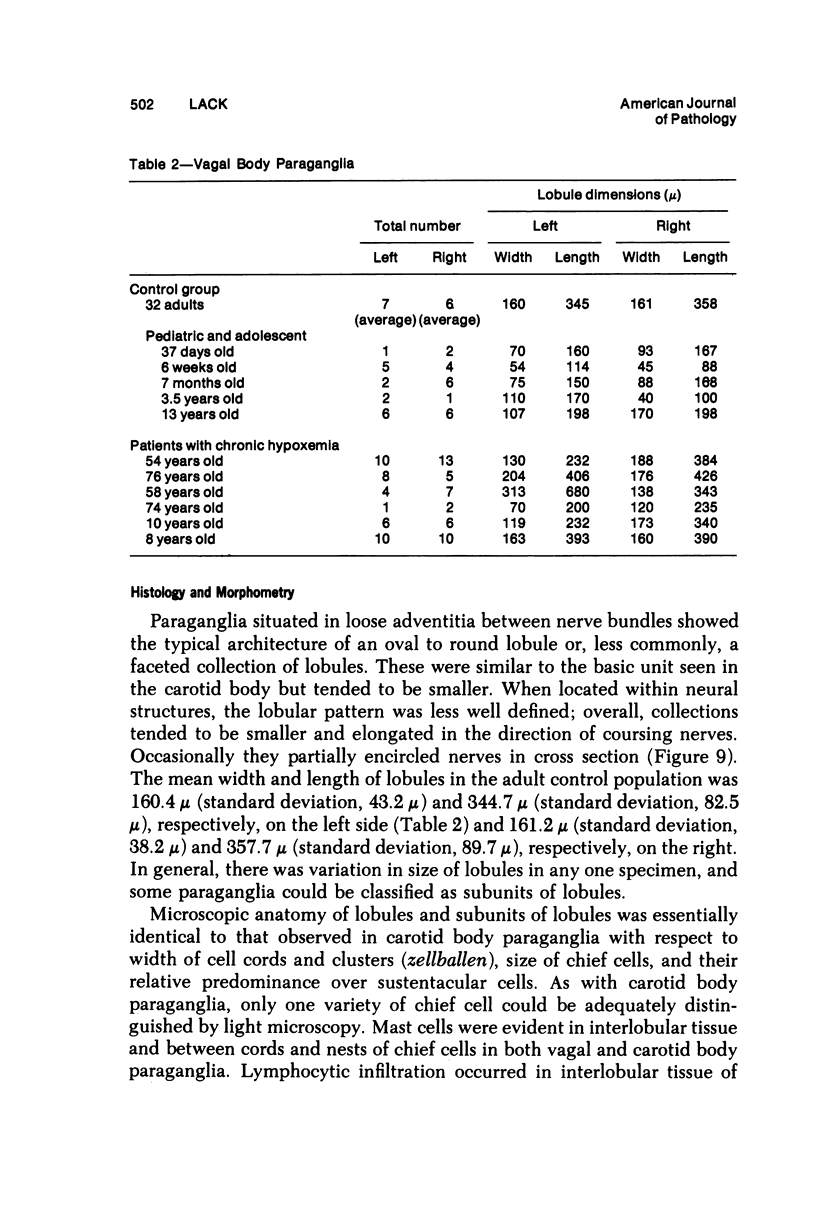

Vagal and carotid body paraganglia were obtained from 43 randomly selected autopsies performed at the National Naval Medical Center. In each case, tissue from both sides was step sectioned and comparatively studied. The mean combined weight of carotid bodies in 37 control patients was 25.9 mg. There was good correlation between size and number of separate paraganglia comprising the vagal body (seven left, six right). Lobules were closely related to the ganglion nodosum and were actually within it in three instances. Tissue resembling parathyroid was encountered within 4 of the 86 resected vagus nerves. Lymphocytic infiltration occurred in carotid and vagal body paraganglia of 28% and 16% of patients, respectively. There was Schwann cell proliferatation in carotid body lobules of 2 patients; in another patient, talc emboli were present. The mean combined weight of carotid bodies in 6 patients with chronic hypoxemia was 47.6 mg, significantly greater than in the control group; in each case, lobules were enlarged. Chief cell hyperplasia occurred in vagal body paraganglia of 2 patients; in two other patients, lobules were large with equal proliferation of constituent cells. These morphologic findings indicate that in patients with chronic hypoxemia some vagal body paraganglia can be ascribed a chemoreceptor role similar to but probably less important than that of the carotid body.